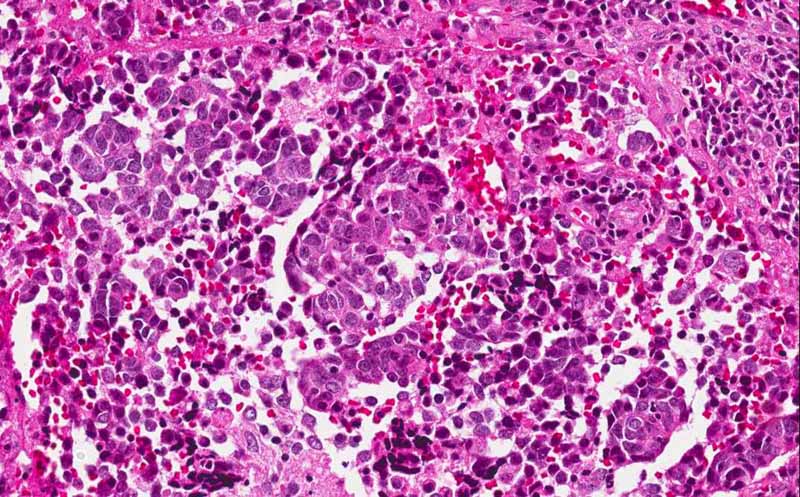

Hematoxylin & eosin

This image was taken at 60x original magnification. The features of a small blue cell tumor is well illustrated here.